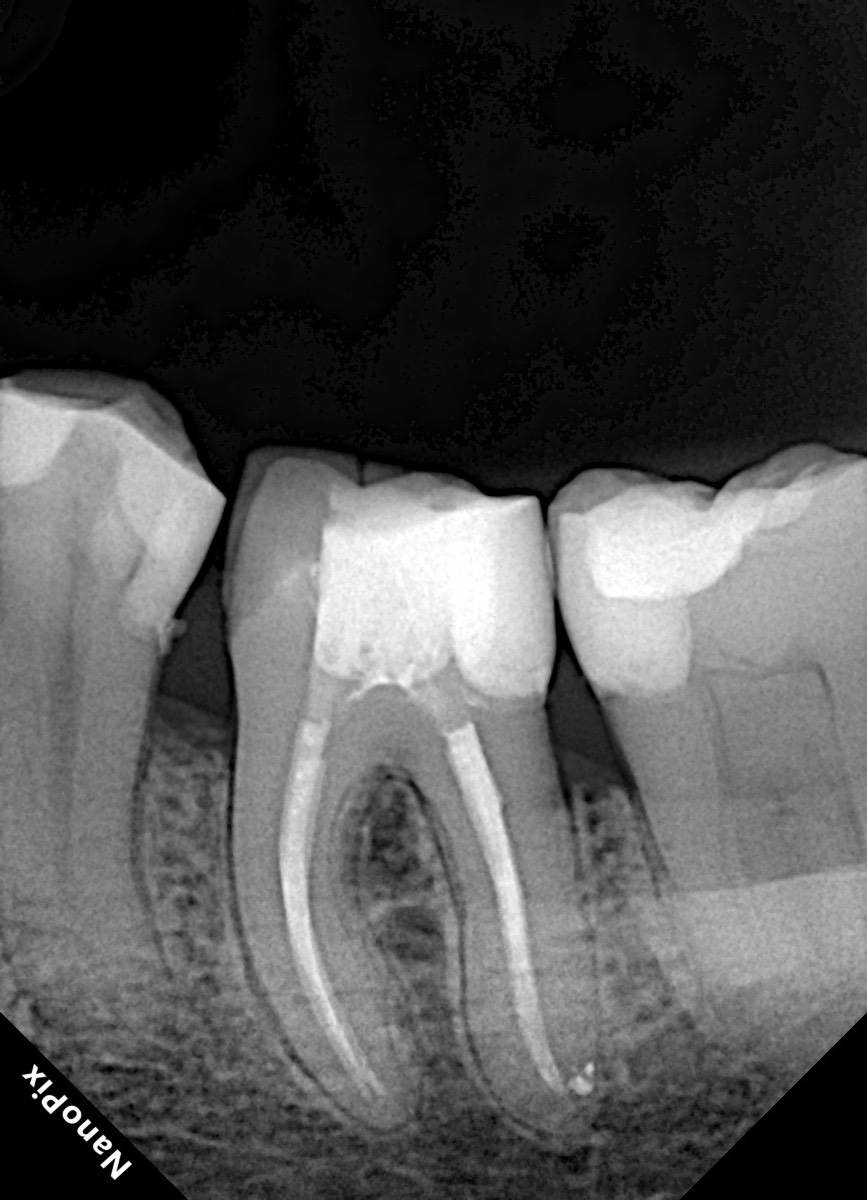

Гарриевич Опубликовано 18 марта Автор Поделиться Опубликовано 18 марта В 13.03.2026 в 15:26, Doc сказал: Круто! То, что вынимается, доктору вернуть надо или в металлолом сдать? :))) Обычно мы сдаем в чернмет, какие никакие деньги)) Реколл 3 года 1 Ссылка на комментарий

Гарриевич Опубликовано 10 часов назад Автор Поделиться Опубликовано 10 часов назад Еще один осмотр спустя 3 года и полное заживление 1 Ссылка на комментарий